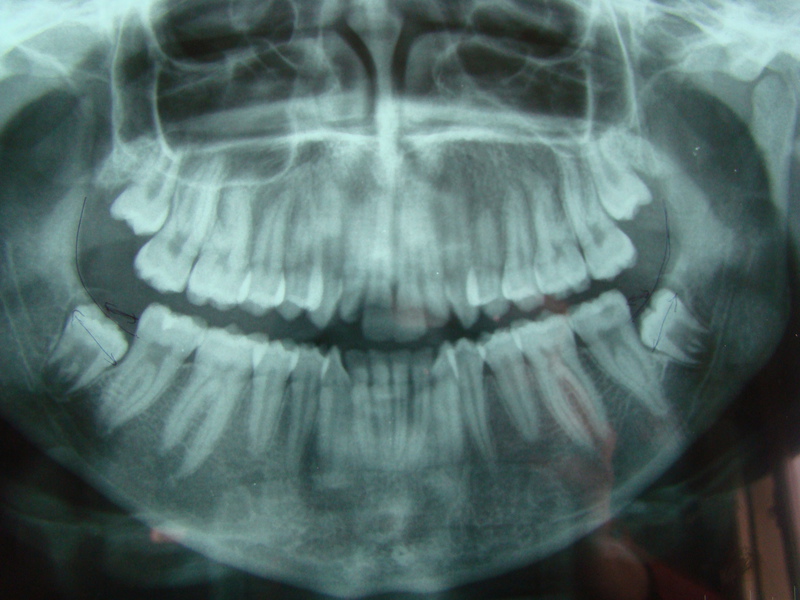

Actuellement, il est souvent proposé de pratiquer l’extraction des dents de sagesse lorsqu’elles sont encore au stade de germes (seule la couronne est formée à l’intérieur de l’os) c'est-à-dire entre 14 et 16 ans environ. Il ne s’agit pas d’un phénomène de mode comme le pense certains. Dès ces âges (et parfois même avant), l’examen clinique et la radiographie de la mâchoire (panoramique dentaire) permettent de dépister les cas où les dents de sagesse ne pourront se positionner correctement sur la mâchoire (manque de place, mal orientation….) et risquent de poser, à l’âge adulte, les problèmes précédemment cités. Au stade de germes, les racines des dents de sagesse ne sont pas encore formées et leur proximité vis-à-vis du trajet du nerf mandibulaire est moindre et donc les risques post- opératoires vis-à-vis de ce nerf également moindre (cf. risque)